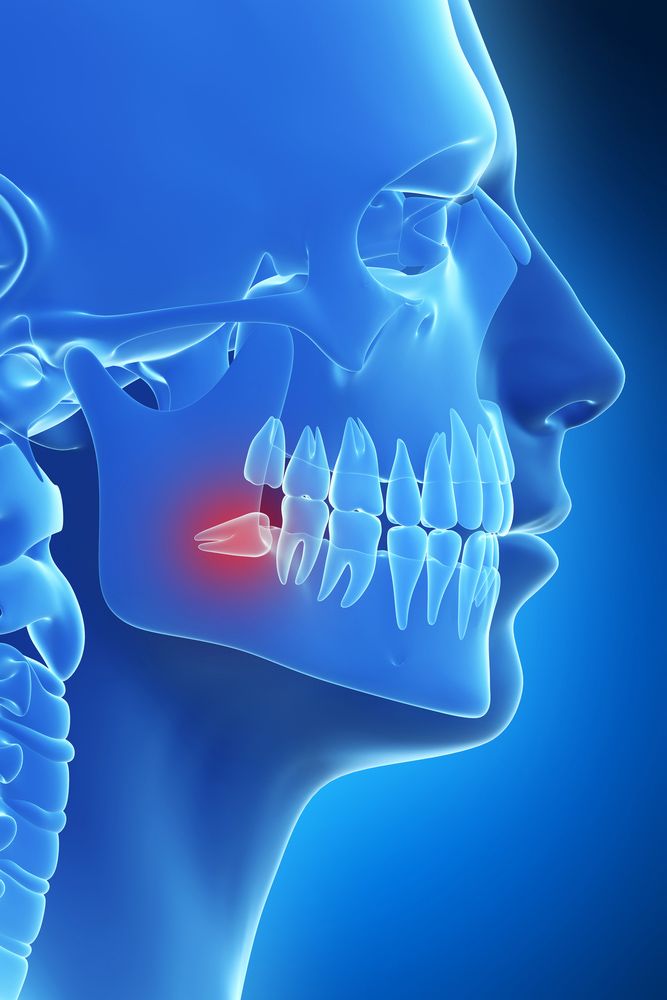

Wisdom Tooth Removal

If you do not have enough room in your dental arch to support wisdom teeth, our dentists may recommend wisdom tooth removal. Extraction can prevent complications like infection, periodontal disease, overcrowding, and misalignment.